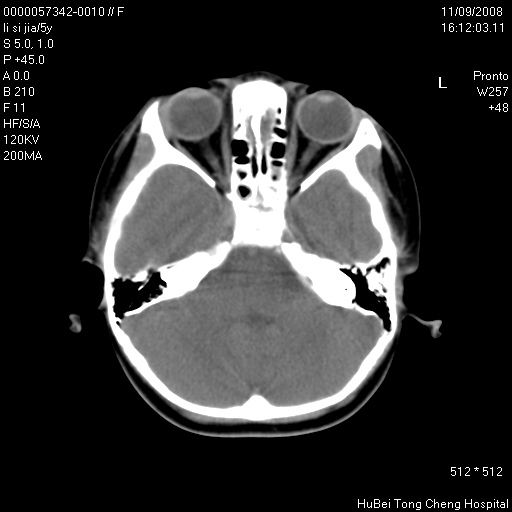

患儿 女,5岁。鼻塞、流涕2年余。

临床诊断:慢性副鼻窦炎?

副鼻窦ct轴位平扫(层厚、层距均为5mm),图像如下:

双侧上颌窦\\筛窦及蝶窦内均可见多量软组织密度影,结合病史支持考虑慢性全鼻窦炎

双侧上颌窦、筛窦及蝶窦内均可见粘膜增厚,结合病史支持考虑慢性全付鼻窦炎,腺样体肥大。